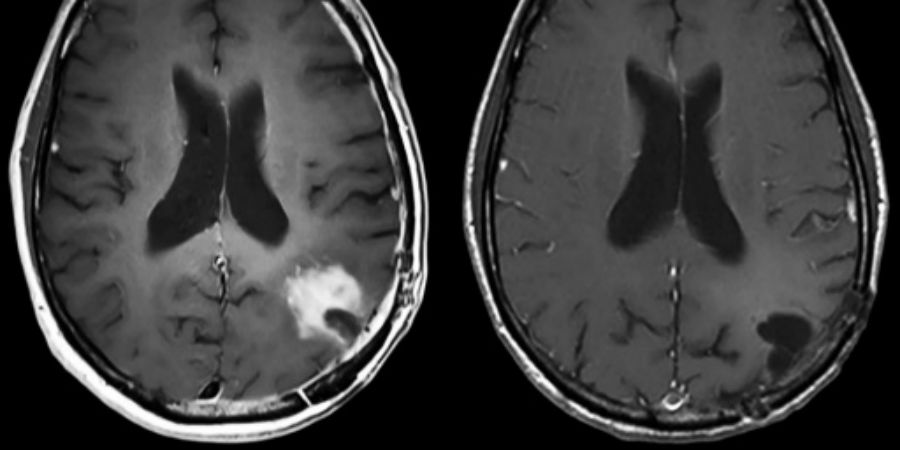

Al na negen maanden is op een MRI-scan van een patiënt te zien dat de tumor is geslonken (zie onderstaande foto). En na drie jaar bleek 21 procent van de behandelgroep nog in leven te zijn tegenover 4 procent van de controlegroep. Na ruim vijf jaar leefden er nog twee patiënten die de behandeling hadden ontvangen.

Beeld: Desjardins et al., The New England Journal of Medicine